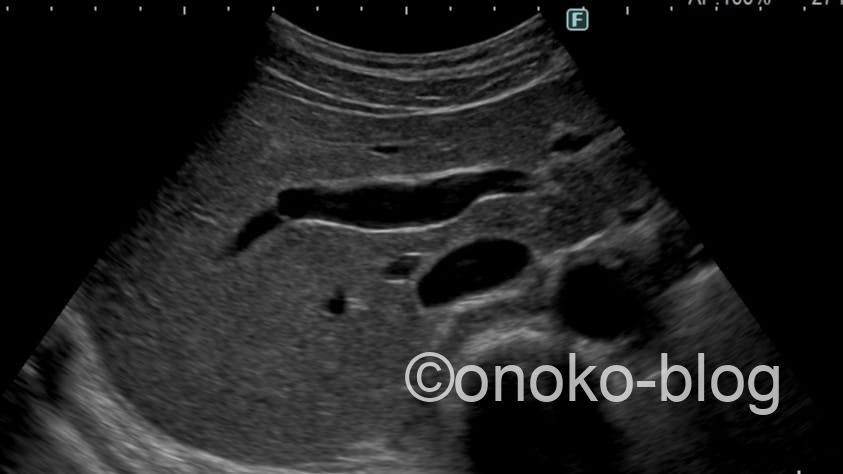

まずは通常のBモード画像。

素晴らしい解像度。キレイですね♡

いちゃもんつけるとしたら私の手技よ… 汗